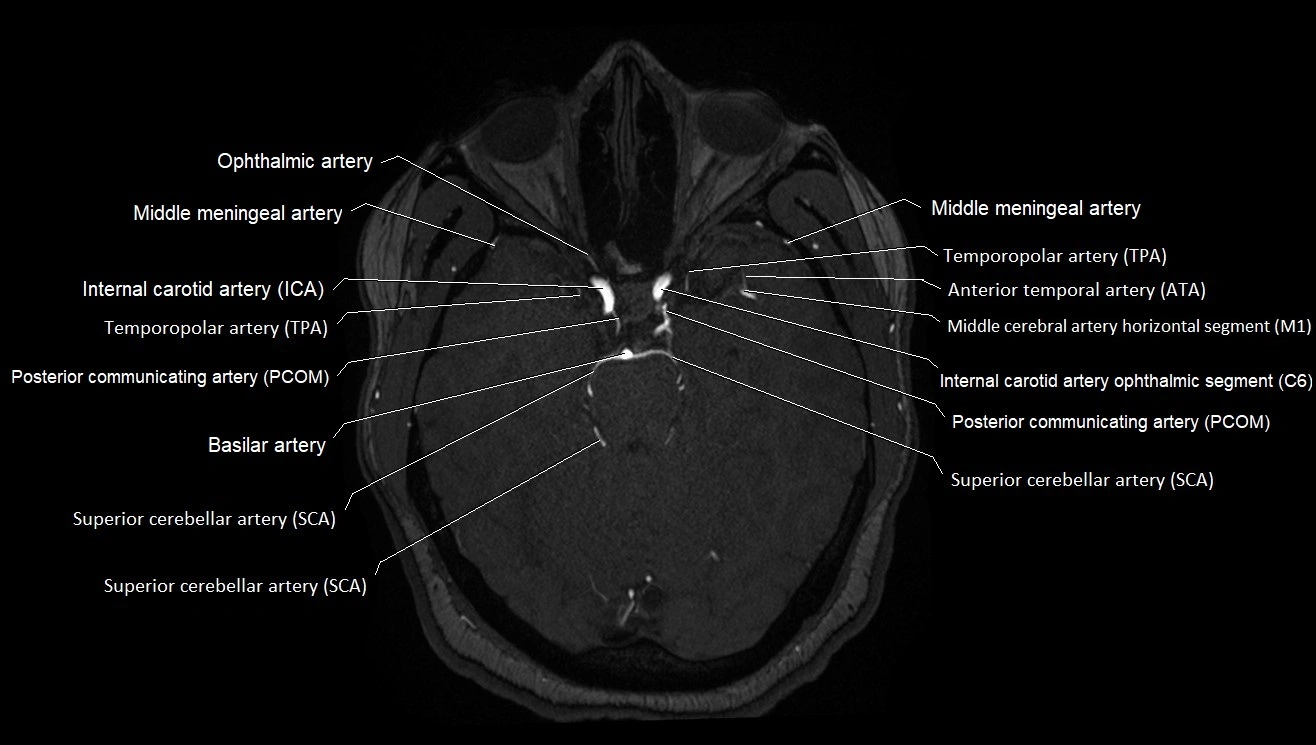

MRA (Magnetic Resonance Angiography):

• Flow-related enhancement makes the AChA appear as a bright, linear vascular signal against suppressed background

• High sensitivity for origin and proximal course; distal branches may be too small to resolve

• Detects stenosis, occlusion, aneurysm, AVM feeders

MRI images

image